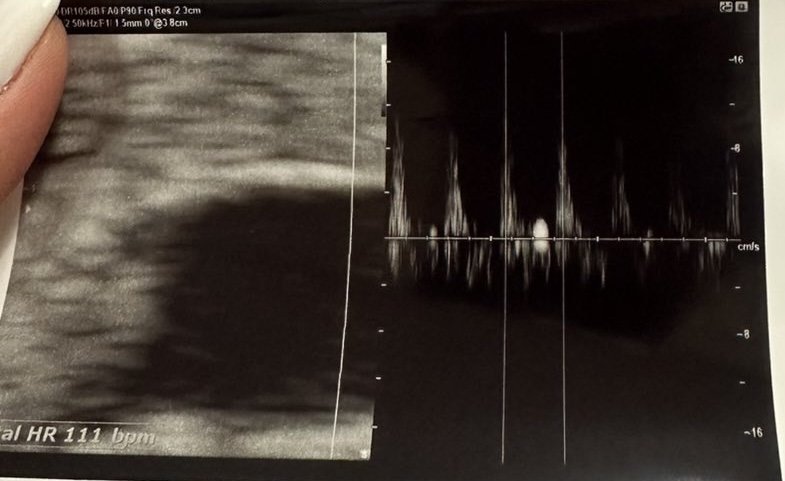

Според вас дали големината на ембриона , е добре за седмицата в която съм? Чухме и пулс. Доктора каза честито, но и накрая на прегледа каза на следващия преглед ще видим дали се развива, което малко ме притесни. Благодаря!

Чухме пулс.